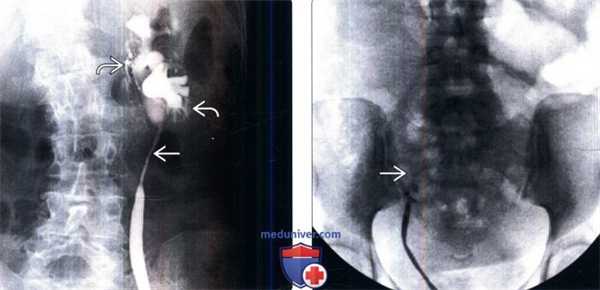

(Слева) Ретроградная пиелография: стриктура длинного сегмента проксимального отдела мочеточника с расширением чашечек. Обратите внимание на интравазацию контраста указывающую на перерастяжение собирательной системы под давлением. Эта стриктура образовалась после хирургической экстракции камня из мочеточника.

(Справа) Ретроградная пиелография: полная обструкция правого мочеточника на уровне входа в таз. Эта стриктура является следствием повреждения мочеточника при гинекологической операции. Такие признаки обнаружены на антеградной пиелографии (изображение отсутствует).

• Уретерография (пиелография): антеградная или ретроградная:

о Считается золотым стандартом, подтверждающим наличие и описывающим признаки повреждения мочеточника

о Антеградная (через нефростому); ретроградная (посредством цистоскопии)